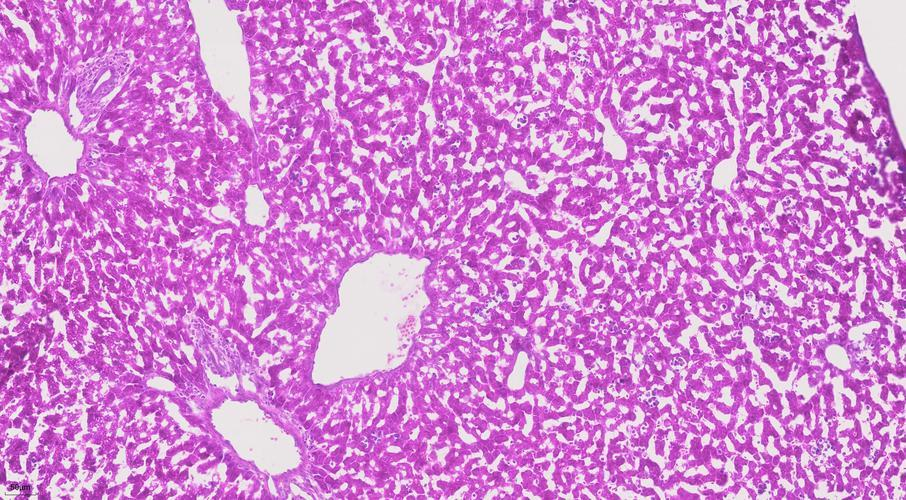

Following a series of processes—fixation, dehydration, and paraffin embedding—the patient's tissue is meticulously sectioned into 4-micrometer-thick slides. Subsequently, hematoxylin and eosin (H&E) staining is applied, rendering cell nuclei vivid blue while staining cytoplasm pink. Under the optical microscope, these stained cells revealed their morphological pathological alterations for the first time. Pathologists could visually observe the shape, size, arrangement, and distinctive features of cell nuclei.